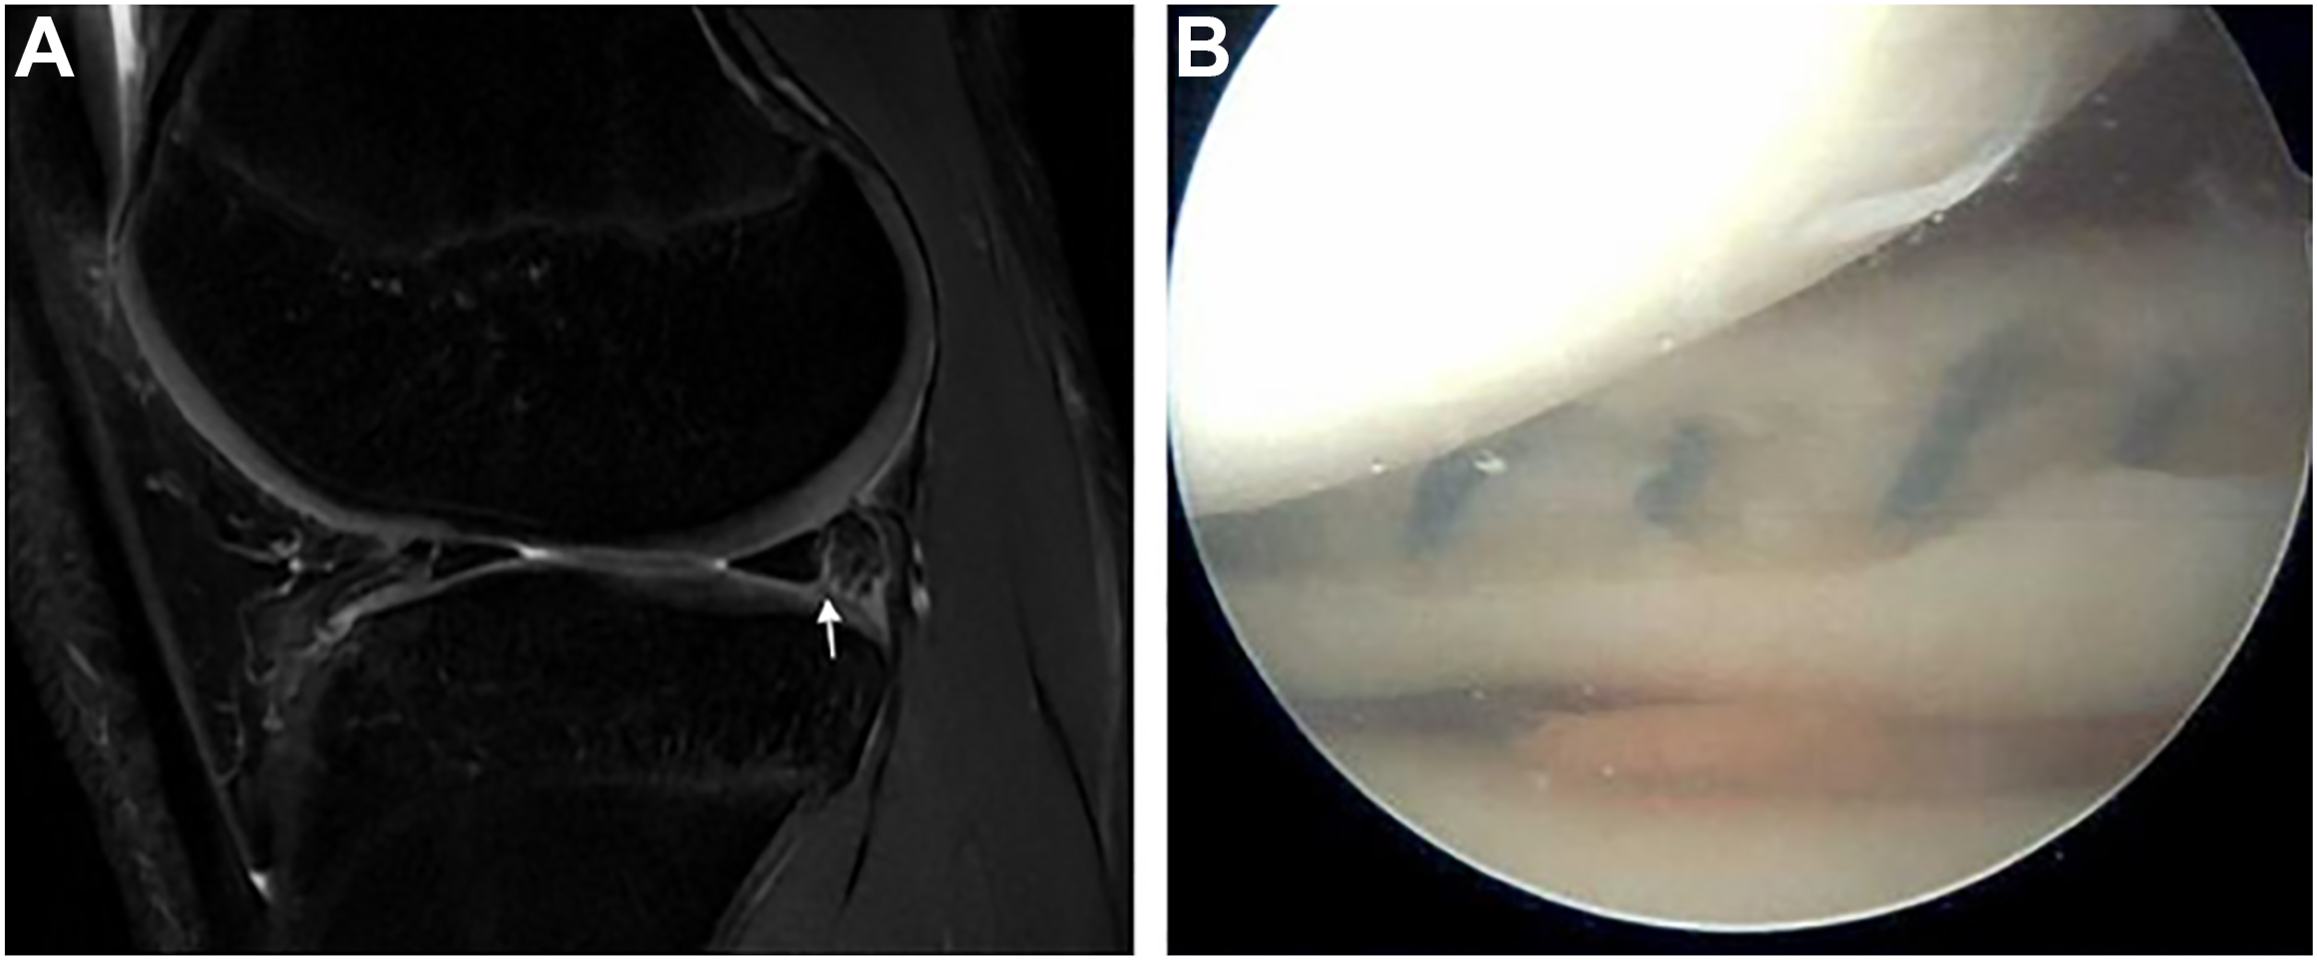

Anatomic and demographic risk factors should be taken into consideration when deciding whether to treat first-time patellar dislocations acutely or postpone surgery to the offseason. The senior author finds several prediction models and scoring systems to be helpful when counseling athletes on this decision. First, a prediction model has been developed to recommend treatment based on the 4 recurrence risk factors with the highest odds ratios ( Table 2 ). These include trochlear dysplasia, history of contralateral dislocation, skeletal immaturity, and Caton-Deschamps index greater than 1.45. Second, the patellar instability severity score can be used to determine which patients may be at higher risk of recurrence based on 6 risk factors ( Table 3 ). Athletes who are at lower risk of recurrence based on these models may succeed with conservative treatment or can postpone surgery to the offseason, whereas those who are at higher risk may require acute surgical stabilization with concomitant osteotomy to realign the joint.